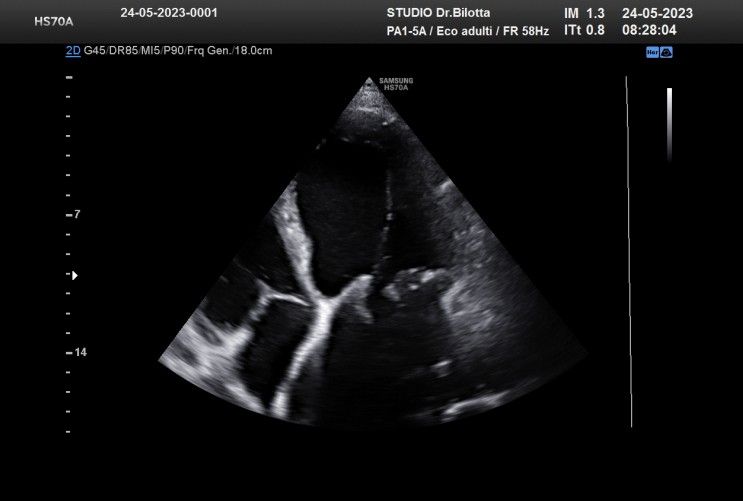

Diploma di maturità classica. Laurea in Medicina e Chirurgia con Lode a 26 anni. Specialista in Oncologia Generale Diagnostica e Preventiva con Lode a 31 anni. Specialista in Malattie Cardiovascolari a 36 anni. Medico generalista dal 1990 poi ospedaliero per trent'anni dal 1993 al 2022 nel corso dei quali ho refertato oltre 100 mila tracciati elettrocardiografici, effettuato oltre 30 mila consulenze specialistiche, praticato circa 10 mila esami ecocardiografici, condotto oltre 2 mila test ergometrici sia su cicloergometro che su treadmill, visionato circa 1500 esami Holter Ecg e ABP ( Ambulatory Blood Pressure ) occupandomi prevalentemente di prevenzione cardiovascolare, ipertensione arteriosa, cardiopatia ischemica, valvulopatie. Dal 2023 ho deciso di trasferire le mie competenze nella libera professione presso il mio studio privato che è stato allestito in linea alle moderne esigenze tecnologiche. Metodiche diagnostiche attualmente praticate: Elettrocardiografia a riposo, Ecocardiografia mono-bidimensionale, PW, CW, Colordoppler tridimensionale, GLS Strain Speckle tracking, Monitoraggio Holter Pressorio delle 24 ore, Monitoraggio Holter ECG 12 canali dinamico delle 24 ore.

Foto e video